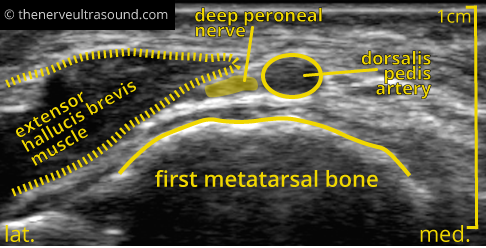

In the same section the deep peroneal nerve may be seen in the depth near the anterior tibial artery.